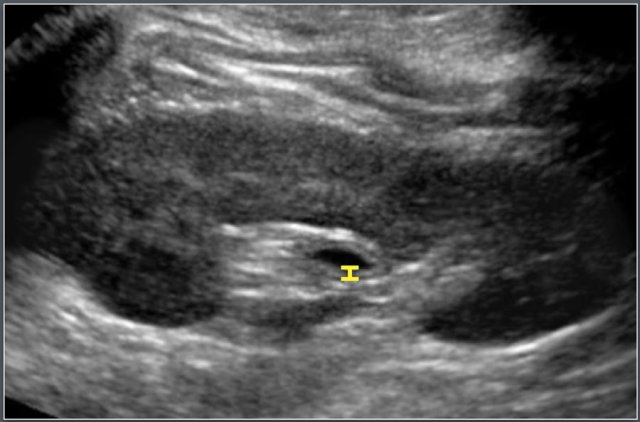

Bowel

Adapted from reference 13 Adapted from reference 13

Materials and method

The study population consisted of 128 patients (57 male and 71 female).

Of this population 86 were between the ages of 1-19 years (only data pertaining to this selection is presented).

Bowel wall thickness was measured on transverse sections and comprised of mucosa, lamina propria, muscularis mucosa, submucosa, and muscularis propria.

Ultrasonographic measurement of wall thickness of terminal ileum in a 12-year-old boy with cystic fibrosis.

Causes of small bowel wall thickening:

• Henoch Schönlein Purpura

• Crohn's disease

• Lymphoma

In the same study the wall thickness of the colon was measured.

Causes of colon wall thickening:

• Inflammatory bowel disease (IBD)

• Hemolytic Uremic syndrome

• Pseudomembranous colitis